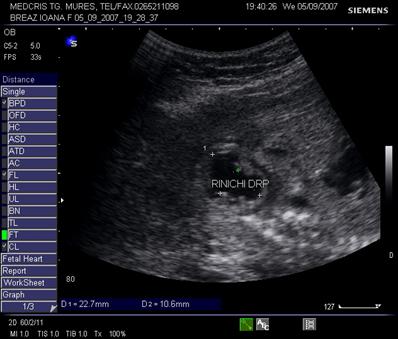

Fig. nr. 274. Sectiune transversala fetala la nivel lombar, 23 sapt., linia verde indica rinichiul fara dilatatie, cu sageata se remarca dilatatia pielocaliceala evidenta controlaterala

Fig. nr. 275. Dilatatia pielocaliceala din figura precedenta , intr-o sectiune parasagitala fetala, cu axul lung renal.

Fig. nr. 276. Megaureter, la 23 sapt la acelasi fat din figurile precedente.